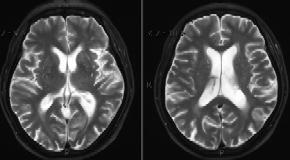

医学影像学(2019春)

医学影像学(2018春)

医学影像学(2017春)